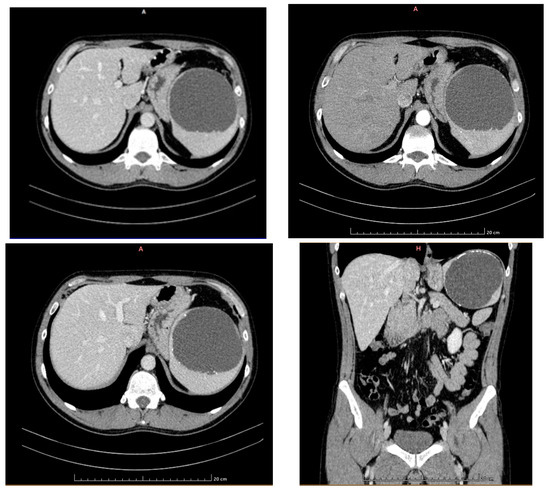

2. Case Presentation

- Capillary hemangioma hepatic segment VII of 8 mm diameter.

- Grade I splenomegaly with simple voluminous splenic cyst, 10 cm in diameter.

- Accessory spleen adjacent to the lower pole of the spleen.